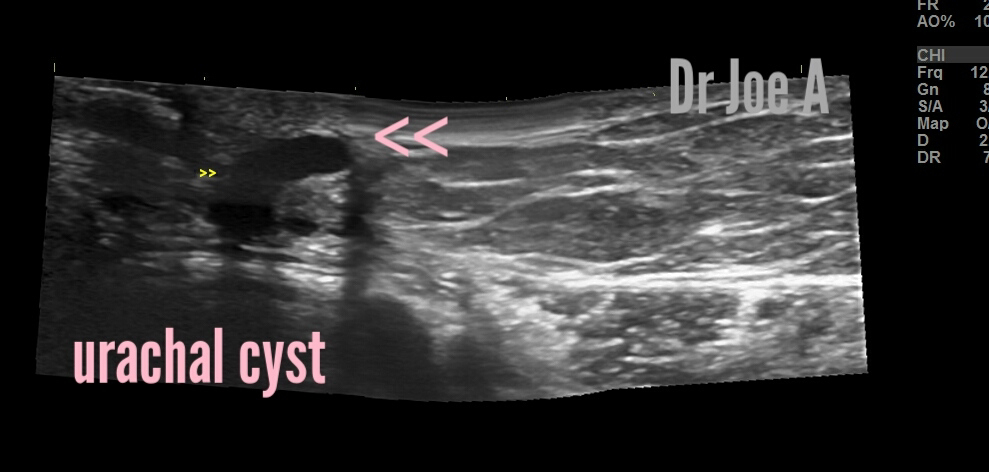

A 24-year-old female presented with abdominal discomfort and a 1 cm-sized cyst within the abdominal wall just to the left of the umbilicus. She had no significant past medical or surgical history, and no family history of similar symptoms. An ultrasound was performed, which showed an elongated cystic lesion just to the left of the umbilicus, consistent with a urachal cyst. The patient was referred for further evaluation and management.

Ultrasound Findings:

The ultrasound findings in this case are consistent with a urachal cyst. The following were the characteristics of the cyst on ultrasound:

1. An elongated cystic lesion just to the left of the umbilicus within the abdominal wall.

2. The cyst had well-defined margins, and was hypoechoic, meaning it appeared darker than the surrounding tissue.

3. The cyst was fluid-filled and contained no solid components.